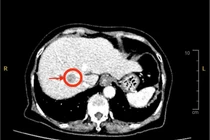

Đau nhẹ vùng thượng vị, đi khám phát hiện u gan phức tạp

Ung thư gan phát hiện sớm có thể điều trị khỏi bằng phẫu thuật hoặc can thiệp. Khi u lớn hoặc xâm lấn mạch máu, việc điều trị sẽ rất khó khăn, tiên lượng xấu.

Cảm thấy đau nhẹ vùng thượng vị, cụ bà 73 tuổi đi khám thì phát hiện có khối u gan phức tạp trên nền xơ gan lâu năm. May mắn nhờ được phát hiện sớm, các bác sĩ Bệnh viện Đa khoa Xuyên Á đã phẫu thuật cắt bỏ khối u, giúp bà điều trị triệt căn ung thư nguyên phát tế bào gan.

Câu chuyện của bà là lời cảnh tỉnh cho nhiều người bệnh gan mạn tính, đừng chủ quan với những triệu chứng nhỏ như cơn đau vùng thượng vị,…